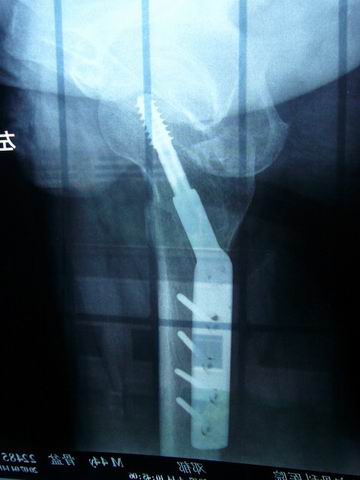

主题:我大腿里取出的钢板-----大家注意安全

07年不幸摔伤,固定骨折安钢板,08年取钢板,不仅经受了痛苦,而且花费了近20000银子,等于损失了一个好自行车,可惜啊!!

图片点击可在新窗口打开查看此主题相关图片如下:p1020984.jpg

图片点击可在新窗口打开查看此主题相关图片如下:p1020986.jpg